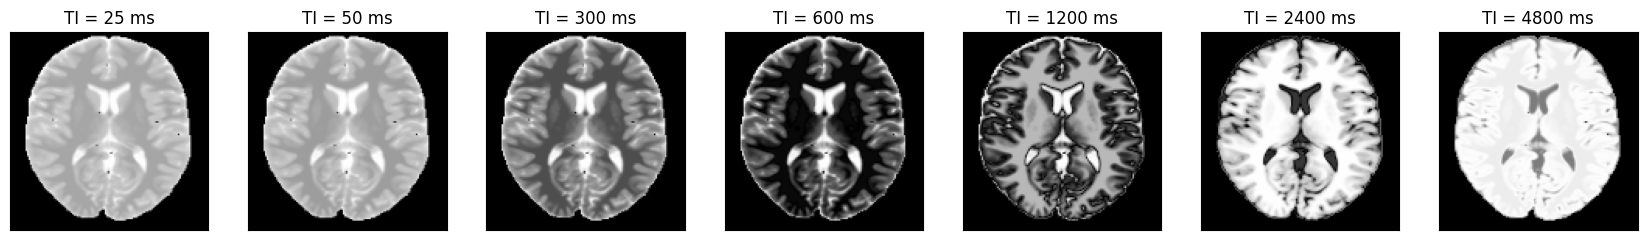

Estimate the T1 maps#

We use a dictionary matching approach to estimate the T1 maps. Afterward, we compare them to the input and ensure they match.

dictionary = DictionaryMatchOp(InversionRecovery(ti=idata.header.ti), index_of_scaling_parameter=0)

dictionary.append(torch.tensor(1.0), torch.linspace(0.1, 5.0, 1000)[None, :])

m0_match, t1_match = dictionary(idata.data[:, 0, 0])

t1_input = np.roll(rearrange(phantom.T1.numpy().squeeze()[::-1, ::-1], 'x y -> y x'), shift=(1, 1), axis=(0, 1))

obj_mask = np.zeros_like(t1_input)

obj_mask[t1_input > 0] = 1

t1_measured = t1_match.numpy().squeeze() * obj_mask

fig, ax = plt.subplots(1, 3, figsize=(15, 3))

for cax in ax:

cax.set_xticks([])

cax.set_yticks([])

im = ax[0].imshow(t1_input, vmin=0, vmax=3, cmap=Colormap('lipari').to_mpl())

fig.colorbar(im, ax=ax[0], label='Input T1 (s)')

im = ax[1].imshow(t1_measured, vmin=0, vmax=3, cmap=Colormap('lipari').to_mpl())

fig.colorbar(im, ax=ax[1], label='Measured T1 (s)')

im = ax[2].imshow(t1_measured - t1_input, vmin=-0.3, vmax=0.3, cmap='bwr')

fig.colorbar(im, ax=ax[2], label='Difference T1 (s)')

relative_error = np.sum(np.abs(t1_input - t1_measured)) / np.sum(np.abs(t1_input))

print(f'Relative error {relative_error}')

assert relative_error < 0.01

Relative error 0.004718553740531206